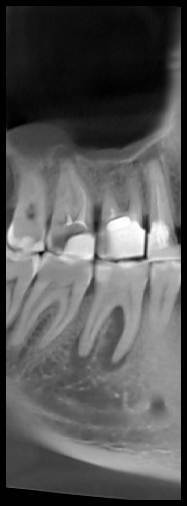

КТ от 28.05.2024

28_05.24(2).jpg.0ffa1febe861106733e1de830afbe6f4.jpg28_05.24-1(2).jpg.9c45d7be16aeed505bd413ce9bc6e69e.jpg28_05.24-2.jpg.a728a7d7e6213c1c8302b43adc89e4d0.jpg28_05.24-4(2).jpg.ac43f3448a3988c7006f74e1d0ce09da.jpg28_05.24-6(2).jpg.dd1fd85c6cc0fcd3d43bd9e71fc0d616.jpg28_05.24-8(2).jpg.885c8cb905445e9308f124fb9e5c616b.jpg28_05.24-9(2).jpg.6cceaaaa1b56d0967482c87b951fbe2d.jpg28.5.24-5(2).jpg.b2d79427a16769c9fd4f0d0911a9db8f.jpg28.5.24-7(2).jpg.f6c17f9820e72dc2708955a65a190b57.jpg28.0524-3(2).jpg.0aa9f153071766a340b428158a94ade8.jpg